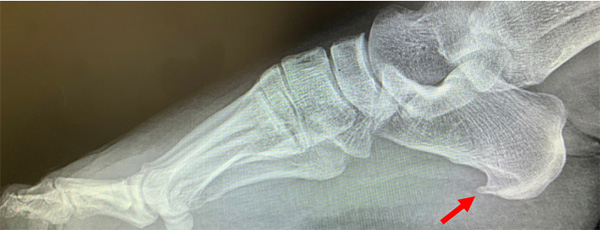

足底筋膜炎可合并平足出现,多数人合并小腿后方腓肠肌紧张的情况,可出现在长期站立或者运动人群,也可出现在不运动的人群。X光片显示往往伴随跟骨下方骨质增生(出现骨刺)。

● X光片可以看到跟腱止点区域骨质增生,跟腱内钙化;